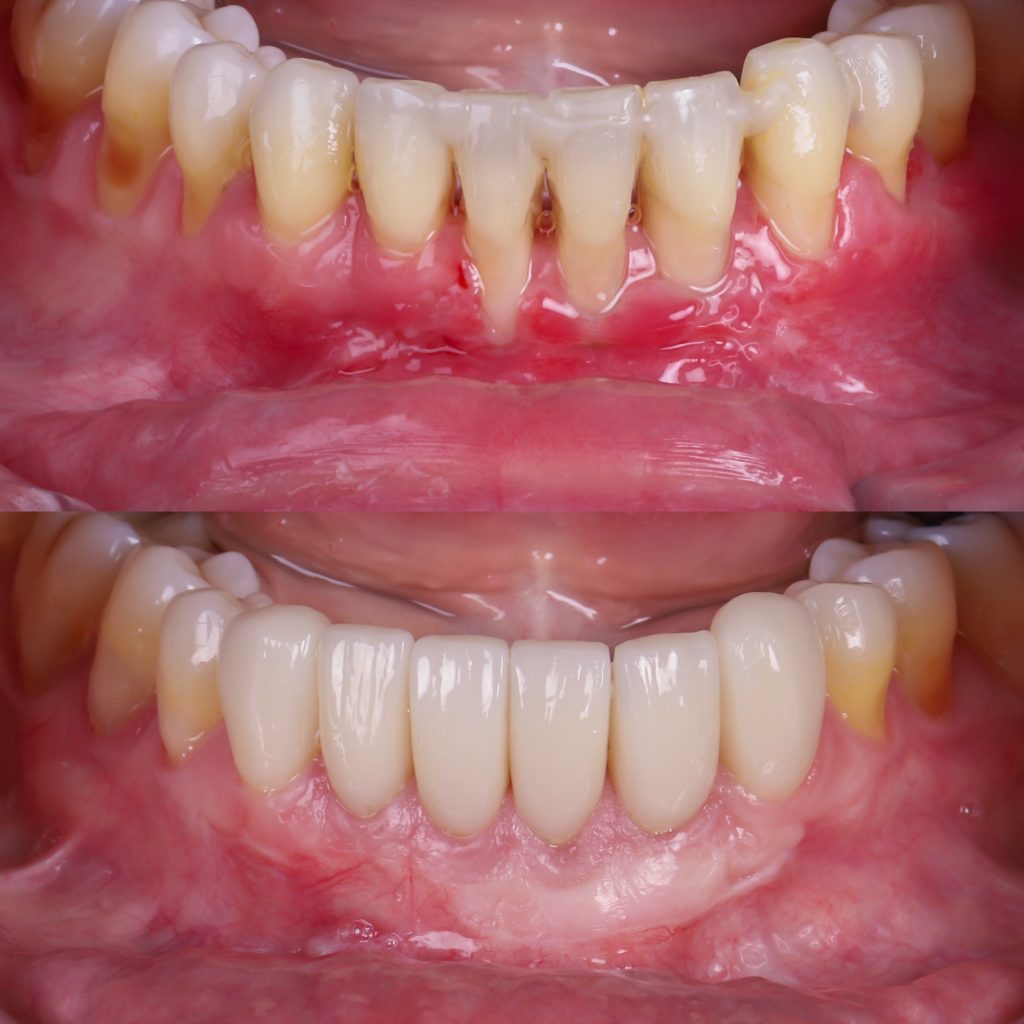

Fotos de encías retraídas antes y después

En las fotos de encías retraídas antes y después del tratamiento puede verse la diferencia:

una encía más gruesa, rosada y firme, y una raíz que vuelve a quedar protegida.

En Alejandro Prieto Dental, documentamos los casos con imágenes clínicas (previo consentimiento del paciente) para mostrar los resultados reales obtenidos con el injerto de encía.

Estos tratamientos logran una mejora estética y funcional visible en pocas semanas.

Encías retraídas: antes y después del tratamiento

El cambio tras el tratamiento es evidente: las raíces dejan de verse, el color se unifica y la sonrisa recupera su armonía.

Las fotos de encías retraídas antes y después muestran una mejora notable tanto estética como funcional.